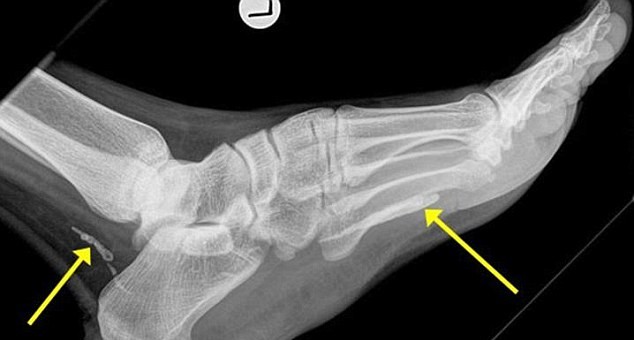

Jonathan Darby, medico specializzato in infezioni, ha notato dalle radiografie due pezzi di verme della Guinea, uno nel piede e uno alla caviglia. Questo verme, ha spiegato il medico, è un parassita che si annida generalmente nell’intestino, dove deposita le sue larve. Un processo che può richiedere anni, spiega il medico: